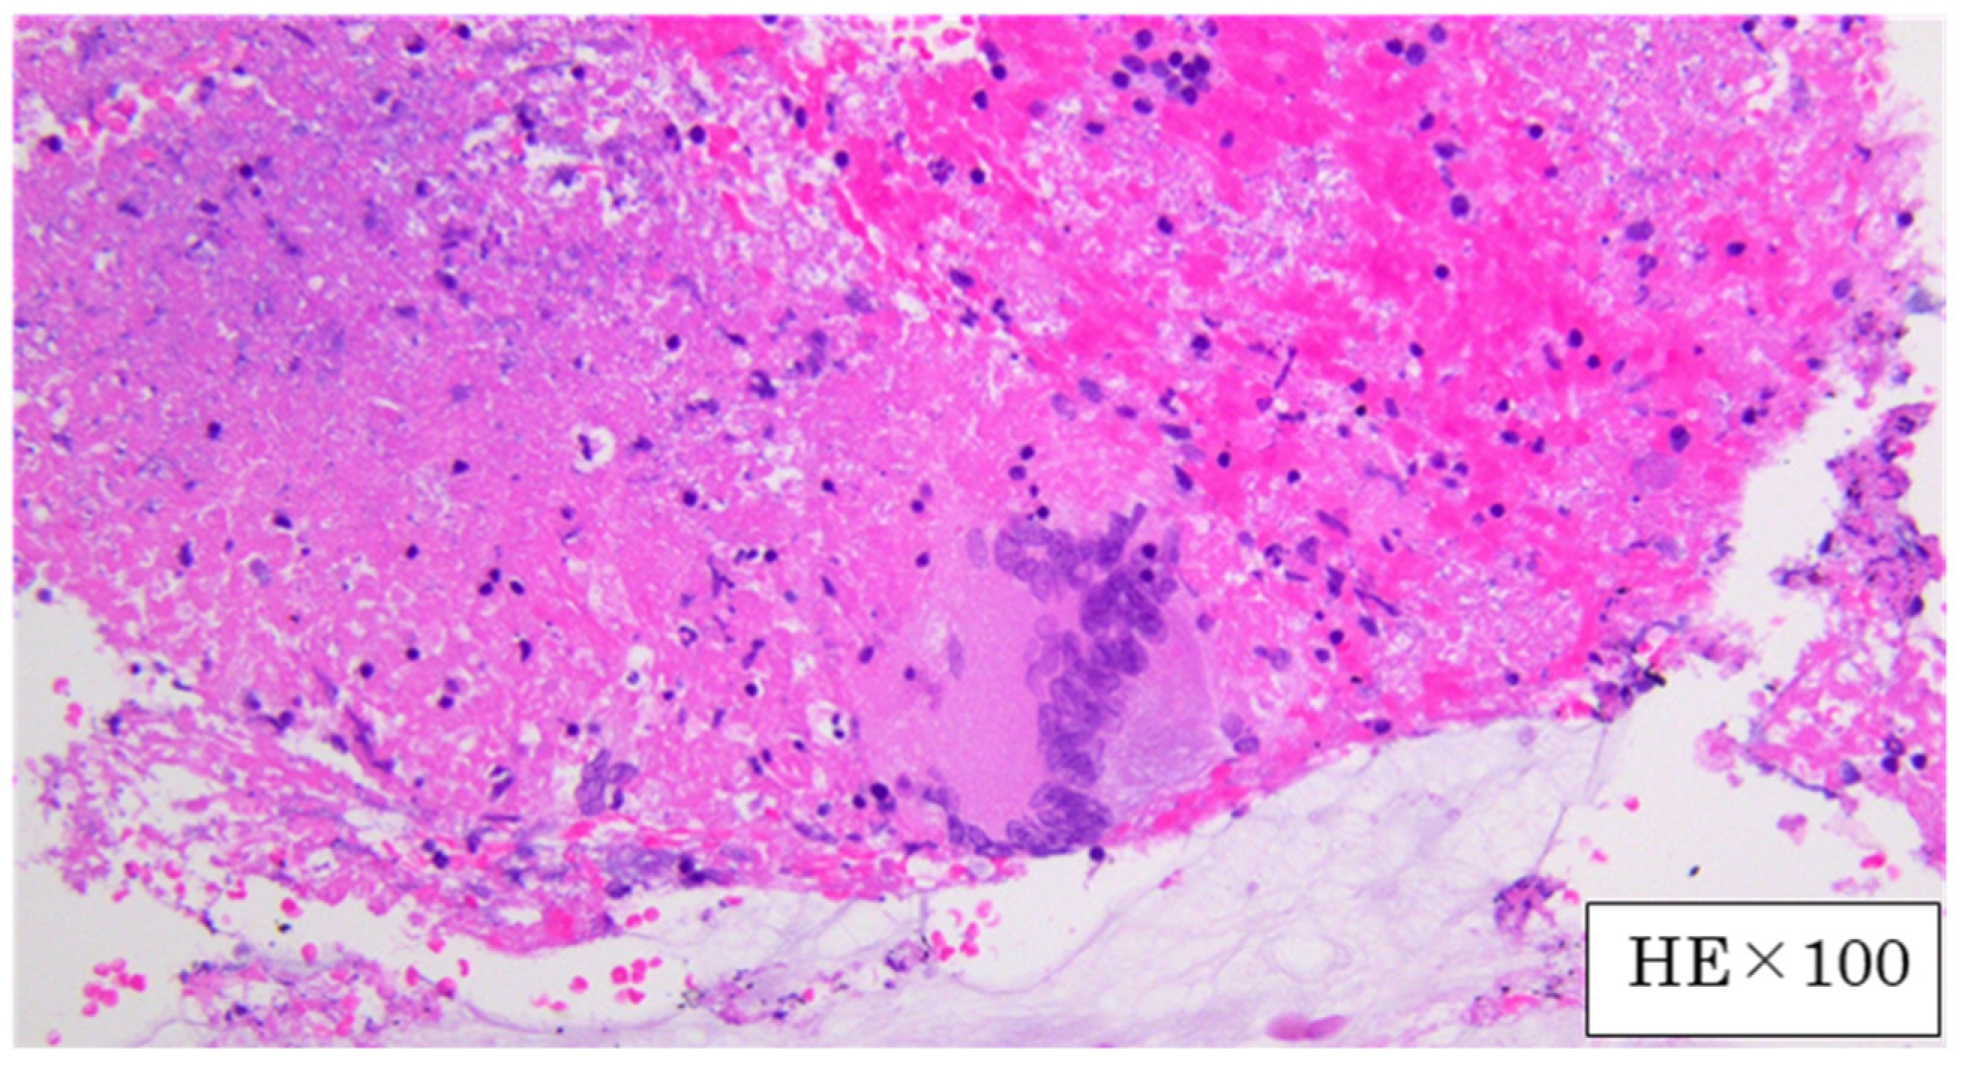

2. Case